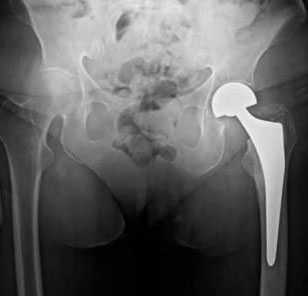

Пациентка Р. 74 года, доставлена в клинику К+31 бригадой СМП в сентябре 2017, травма за 3 часа до поступления, дома, упала на левый бок.

Госпитализирована в РАО, обследована, произведена коррекция водно-электролитных нарушений на протяжении 5 часов, после чего пациентка взята в операционную. Выполнено тотальное эндопротезирование левого тазобедренного сустава.

На вторые сутки госпитализации пациентка переведена в палату стационара. В К+31 пациентам данной категории обеспечивается максимально возможный комфорт и безопасность раннего послеоперационного периода за счёт обеспечения одноместных палат с индивидуальной сиделкой. После курса перевязок, антибиотикопрофилактики, лечебной физкультуры, пациентка былавыписана на амбулаторное долечивание.